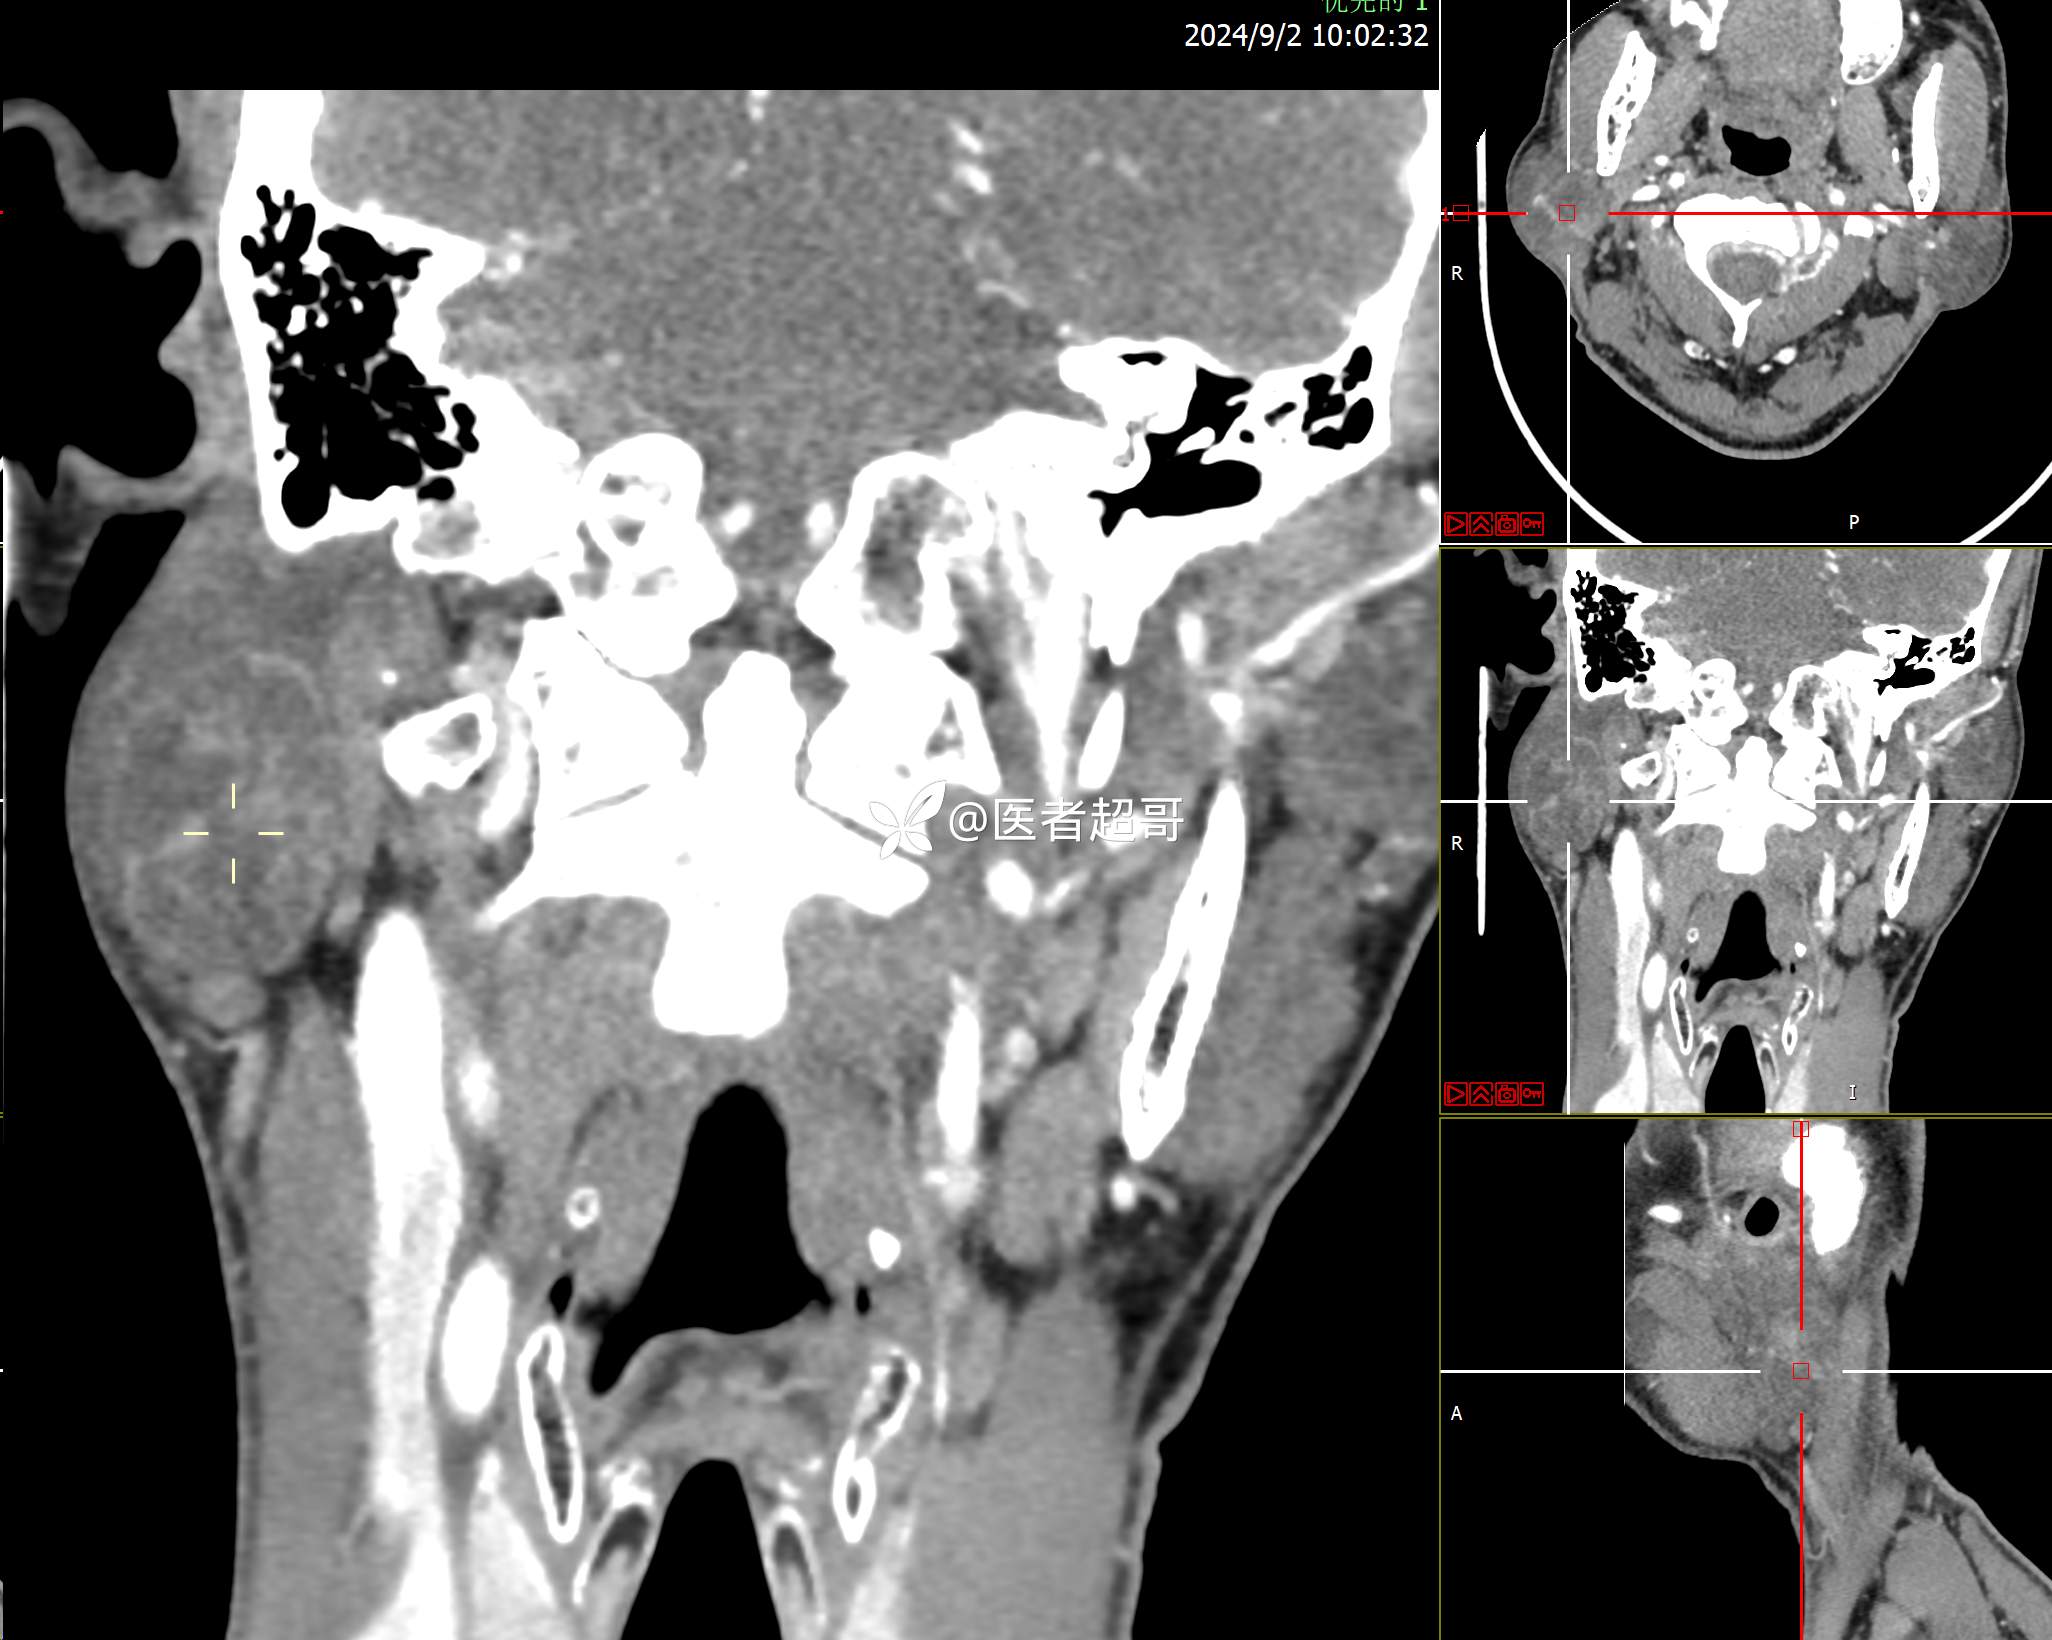

腮腺肿物,CT、MRI齐全,情诊断分析,有详细术程及病理!

主诉:发现右腮腺肿物6个月。

现病史:患者于6个月前无明显诱因发现右侧腮腺区肿物,无疼痛,无局部皮肤破溃,无吞咽困难,无听力下降,无发热,无头痛头晕,患者自发病后在外未治疗,6天前于当地卫生院检查建议手术,为求手术治疗,来我院就诊,门诊以“腮腺肿瘤(右)”收入我院。患者自发病以来,神志清楚,精神可,饮食可,睡眠可,大便正常,小便正常,体重无明显变化。